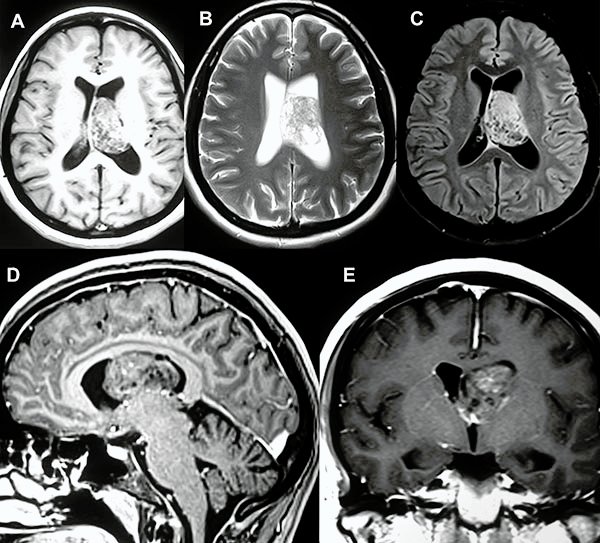

En el estudio de resonancia magnética del encéfalo se observó lesión redondeada, intraventricular a nivel de ventrículo lateral izquierdo, de bordes netos, de aproximadamente 40x30x30 mm, de señal heterogénea, predominantemente isointensa respecto a sustancia gris en T1 con presencia de focos de baja señal en su interior. En T2 se observa lesión predominantemente hiperintensa, múltiples imágenes de aspecto quístico en su interior (aspecto de burbujas) que en el FLAIR dichas imágenes quísticas son atenuadas. Tras la administración de contraste endovenoso se observa moderada y heterogénea captación del mismo (fig. 1).

Figura 1:

A, B y C) Cortes axiales en las secuencias ponderadas en T1, T2 y FLAIR respectivamente. D) Corte sagital de secuencia ponderada en T1 con contraste. E) Corte coronal de secuencia ponderada en T1 con contraste.

En la RM de encéfalo control, realizada 20 días luego de la cirugía, se observa huella de callosotomía anterior sin lesión focal intraventricular residual aparente (fig. 4).

Figura 4:

A, B y C) Cortes axial, sagital y coronal pre quirúrgicos ponderados en T1 con contraste. D, E y F) Cortes axial, sagital y coronal post quirúrgicos ponderados en T1 con contraste.